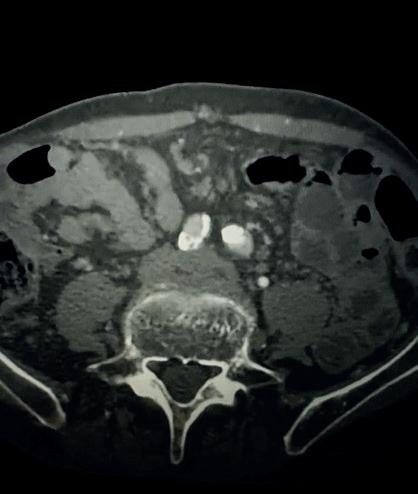

Case 1: The Shockwave L6 device in the setting of FEVAR and complex iliac stenosis

An 82-year-old man with a history of coronary artery disease (CAD), hypertension, hyperlipidemia, and peripheral arterial disease (PAD) presents with rest pain as well as

a large pararenal abdominal aortic aneurysm (AAA). His computed tomography angiography (CTA) revealed very dense and highly diseased iliac vessels with calcium deposition along most of the bilateral common iliac distribution.

The minimum luminal diameter (MLD) of the common iliac arteries measured roughly 4.5mm; however, the

healthy reference vessel diameter (RVD) was 9.5mm. He would require a fenestrated repair of the AAA along with complex iliac stenosis treatment, and extensive bilateral common femoral endarterectomies.

Further, we were concerned we would not be able to advance the 19F fenestrated graft. The endograft was prepared, and then both femoral arteries were exposed. We attempted delivery of the endograft via the right common iliac access. This failed. We then attempted delivery on the contralateral side. Despite multiple attempts, we made little progress. A 10x30mm Shockwave L 6 catheter was selected, and a total of 150 pulses were delivered to each iliac artery at just 4atm. This not only allowed for the delivery of our FEVAR graft but also the full unrestricted expansion of the endograft limbs in the common iliac arteries.

At the completion of the AAA, we took extra time to perform endarterectomies of the deep femoral arteries. His completion CT scan revealed a good seal of the AAA, patency of the renal fenestrations and unrestricted flow to the bilateral femoral arteries.

MLD = 4.5mm RVD = 9.5mm IVL Device Choice = Shockwave L6 10mm

Figure 1. Pre-procdural CTA Figure 4. Graft delivery Figure 1. Pre-procedural angiogram Figure 2. Pre-procedural angiogram Figure 5. Final angiogram Figure 2. IVL treatment angiogram Figure 3. Post-IVL angiogram Figure 6. Post-procedural CTA Figure 3. Final angiogram